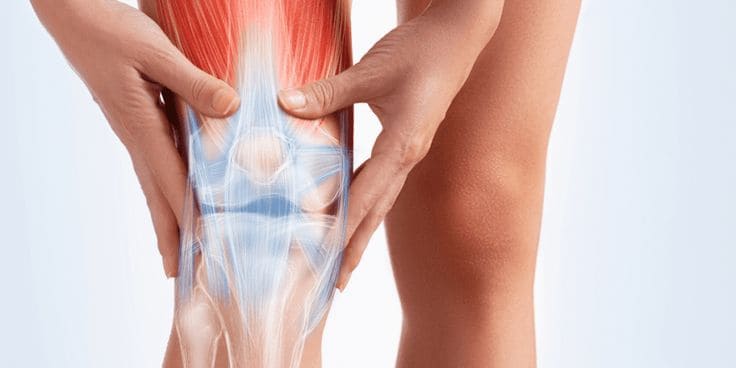

삶의 질을 저하시키는 원인중 하나로 손꼽히는 퇴행성 관절염!

퇴행성 관절염이 오면 우울해지기도 하고 움직이고 생활하는데 큰 불편감을 느끼기도 합니다.